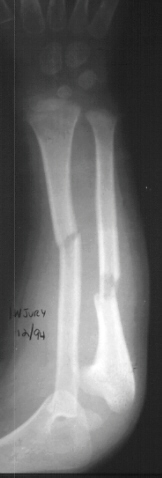

A 4 year and 6 month old male sustained a fall onto an outstretched left arm. He presented to the emergency room with forearm deformity and acute pain(image 1). It was treated with closed reduction and casting (image 2&3).